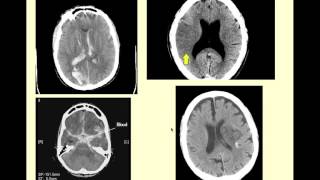

Stroke: Acute infarction - radiology video tutorial (CT, MRI, angiography)

"Stroke Series" video 3 of 7: Acute ischaemic stroke. Presented by Neuroradiologist Dr Frank Gaillard. Find out more: ...

Radiology Channel